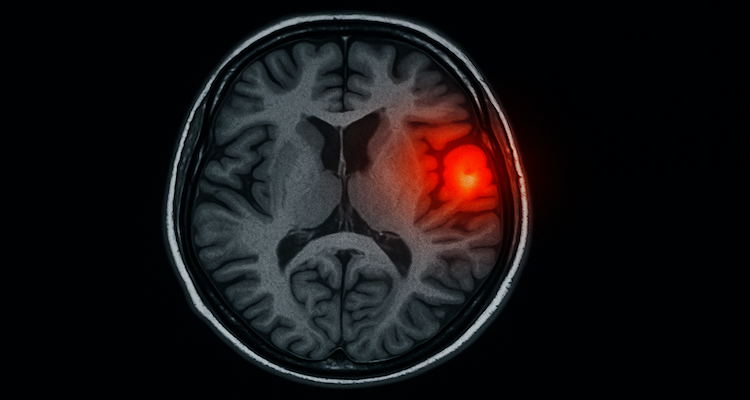

But recent breakthroughs in functional MRI (fMRI) and neurochemical mapping are painting a different picture: one where anxiety isn’t just “in your head” but rather a physical, measurable dysfunction in specific brain regions and networks.

New studies confirm that the amygdala—the brain’s fear center—plays a pivotal role in anxiety, but it doesn’t act alone. The hippocampus, which processes memory, works in tandem with the amygdala to amplify anxious responses by mislabeling neutral experiences as threats. When this loop becomes hyperactive, even a casual social interaction can feel dangerous.

“Study Highlight: A 2024 research paper from Stanford’s Neuroscience Institute revealed that people with Generalized Anxiety Disorder (GAD) had a 30% higher connectivity rate between the amygdala and hippocampus than non-anxious individuals.”